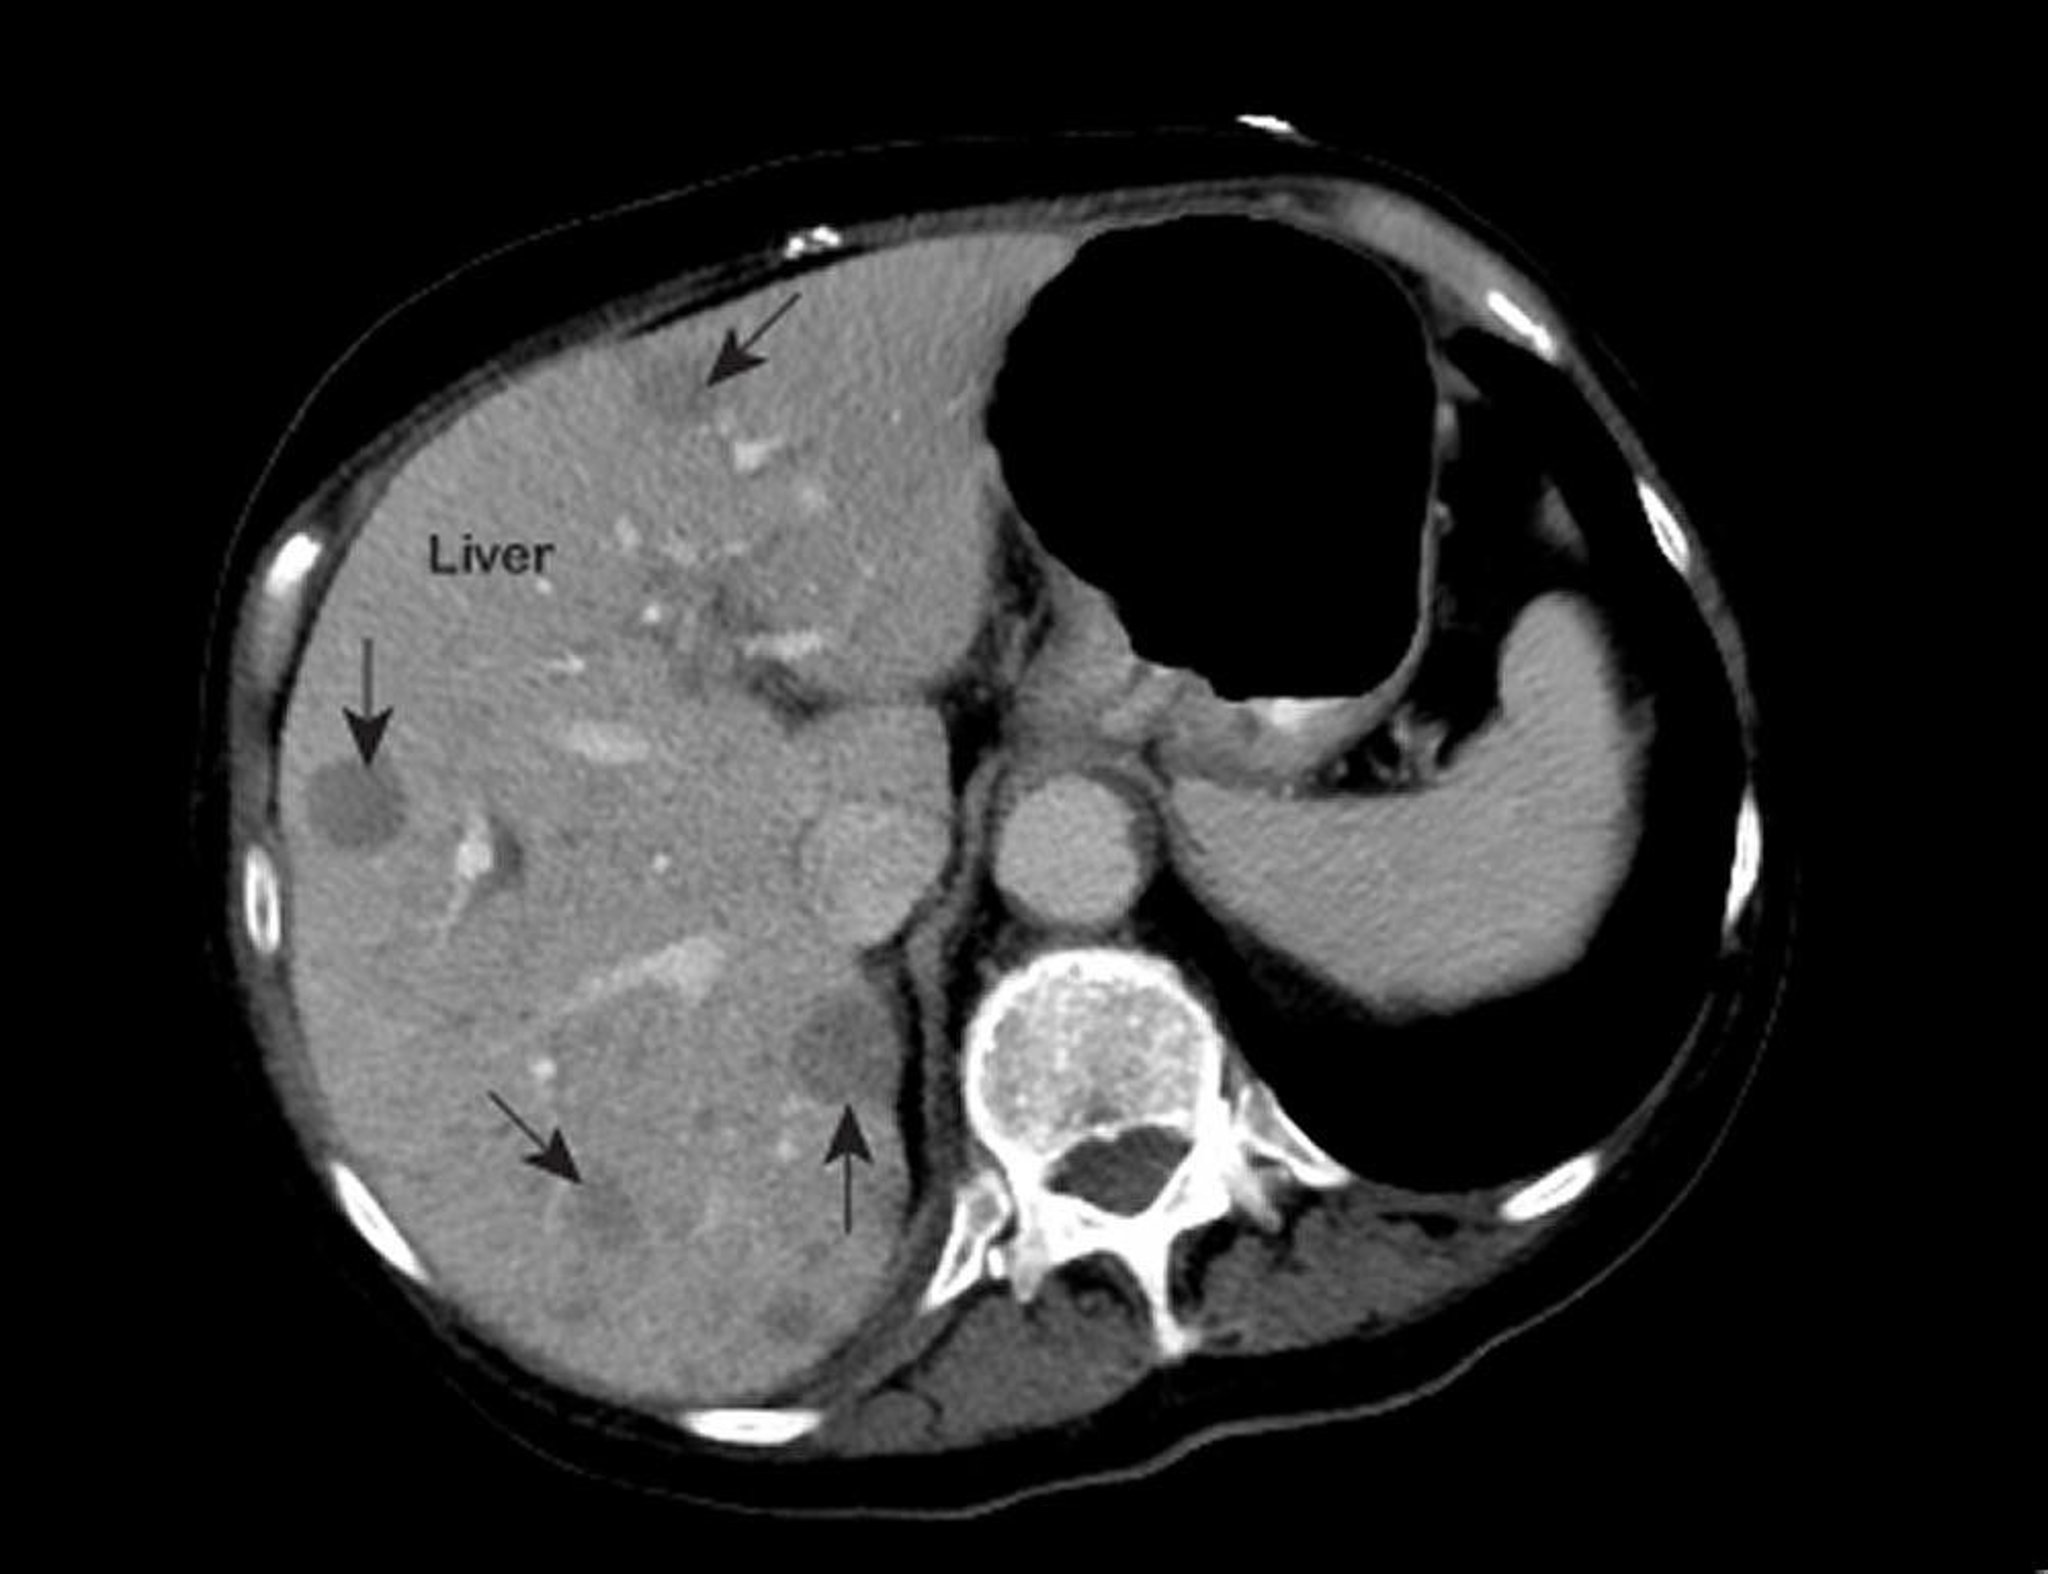

If doctors suspect liver cancer, liver tests, which are simple blood tests, are done to evaluate how well the liver is functioning. Results may be abnormal, as they are in many disorders. Thus, this finding cannot confirm the diagnosis. An ultrasound test is usually helpful, but computed tomography (CT) and magnetic resonance imaging (MRI) of the liver are usually more accurate in detecting the cancer. Before CT or MRI is done, a contrast agent is injected into a vein. The contrast agent helps make abnormalities, if present, easier to see (see Imaging Tests of the Liver and Gallbladder). However, imaging tests cannot always detect small tumors or distinguish cancer from cirrhosis or other abnormalities.